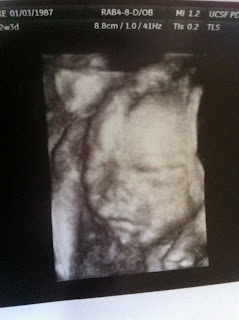

I had my first doctor appointment to confirm pregnancy. They did an ultrasound and that was the first time I saw my baby. I told them I thought my due date was March 17th or somewhere around then. Turns out, I was a day off. I was 9 weeks along and got my official due date...March 18th, 2012. Garrett and I were so excited.

We were so anxious to find out if you were a boy or girl, so we paid for a gender ultrasound. We also got some 3D/4D pictures of you, perks of people knowing your mommy is a nurse. We have video (on daddy's phone I think) of us finding out. Your mommy was faster than the guy doing the ultrasound! Clear as day were your little boy parts! I knew I had to take all the cute girl clothes back. It was a boy. You, were a boy. Finally we could put an identity to you. Daddy sighed a huge sigh of relief. He couldn't handle a little girl first. We told the family that night that you were a boy. Everyone was very excited!

And a 3D/4D ultrasound picture that was done around 22 weeks that looks exactly how he did when he came out!